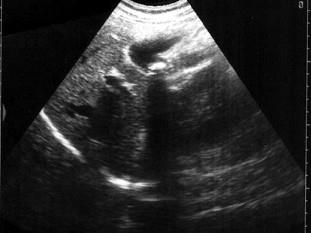

问题 患者女28岁,反复右上腹疼痛二年余,反射肩背部疼痛,B超检查如图所示,根据超声声像图,诊断为?(?)

选项 A.胆囊息肉 B.胆囊癌 C.胆囊结石 D.胆囊蛔虫 E.胆囊腺瘤

答案 C